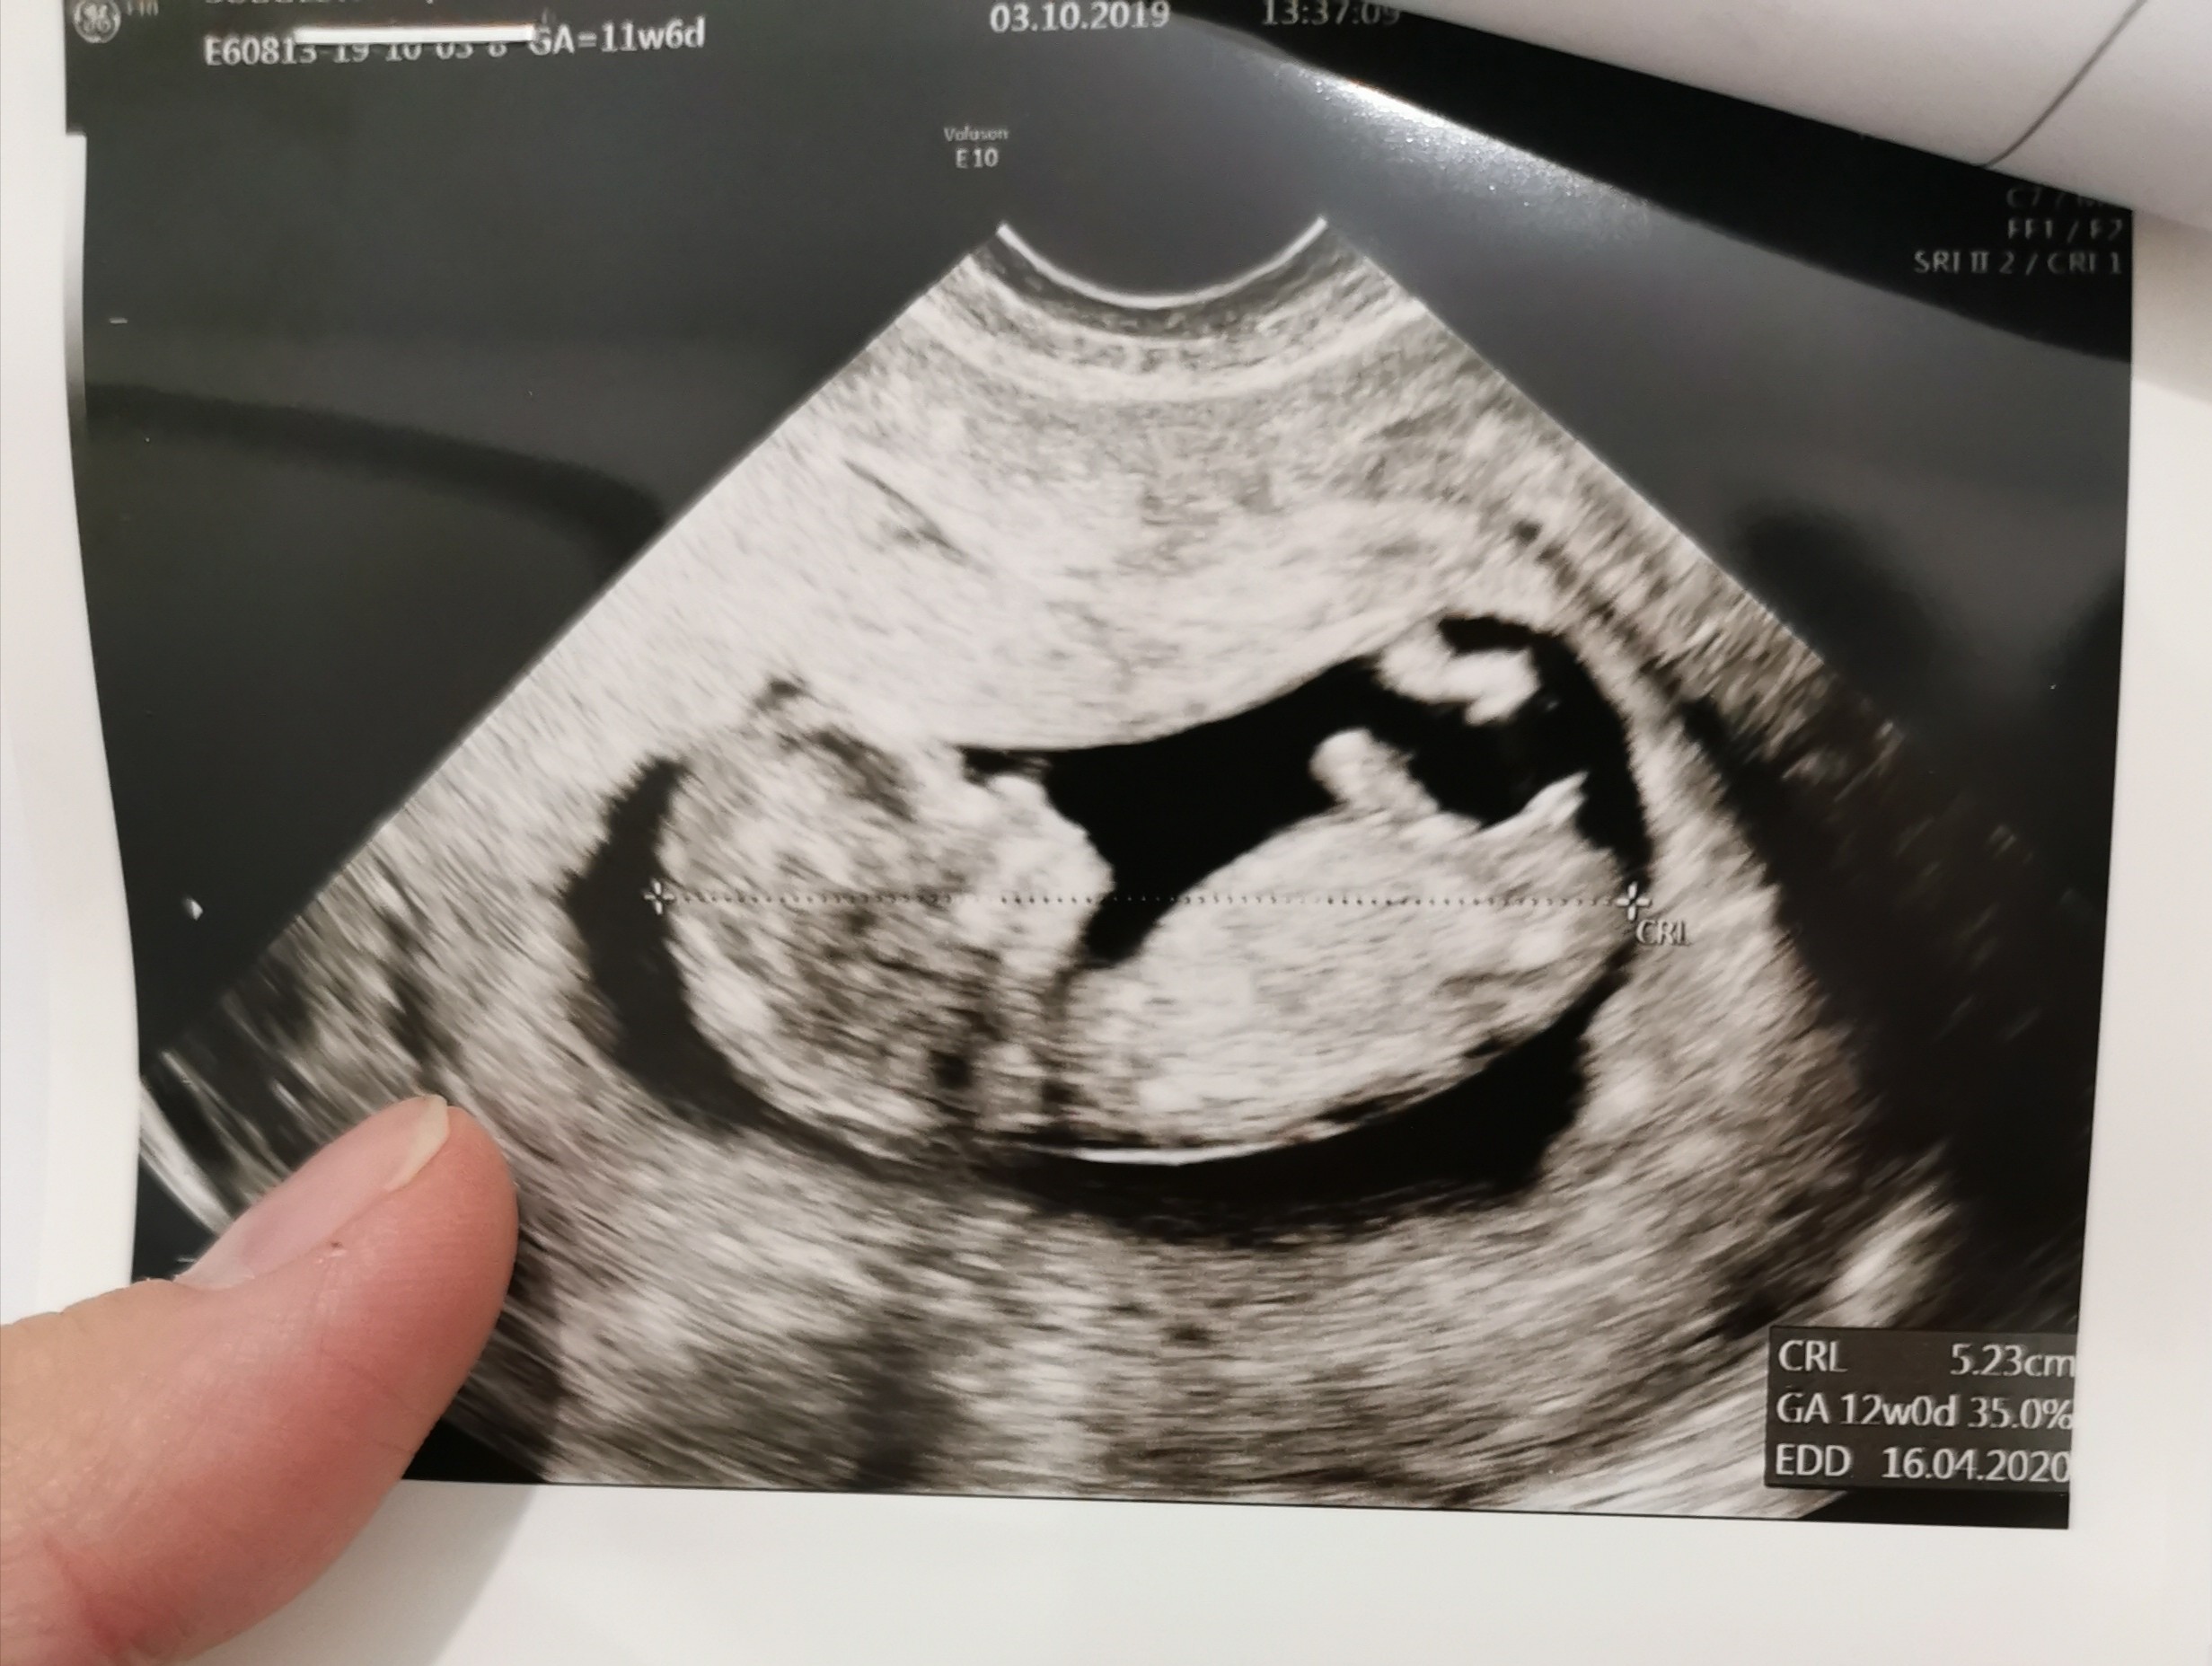

Cześć dziewczyny proszę was o ocenę zdjęcia usg... Miesiąc temu zapowiedzieli mi syna a 4 grudnia na połówkowym ze córka... Trochę mam mętlik w głowie 😞